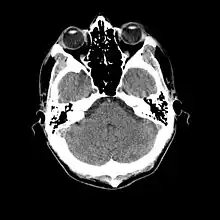

- Cranial computed tomography (CT, invented 1972) proved to be an excellent tool for diagnosing cerebral neoplasms in children, including those found in tuberous sclerosis.[46]

- MR was judged superior to CT imaging for both sensitivity and specificity. In a study of fifteen patients, it identified subependymal nodules projecting into the lateral ventricles in twelve patients, distortion of the normal cortical architecture in ten patients (corresponding to cortical tubers), dilated ventricles in five patients, and distinguished a known astrocytoma from benign subependymal nodules in one patient.[53]

- MR imaging was found to be capable of predicting the clinical severity of the disease (epilepsy and developmental delay). A study of 25 patients found a correlation with the number of cortical tubers identified. In contrast, CT was not a useful predictor, but was superior at identifying calcified lesions.[54]

- Cortical tubers found on MR imaging corresponded exactly to the location of persistent EEG foci, in a study of six children with TSC. In particular, frontal cortical tubers were associated with more intractable seizures.[56]